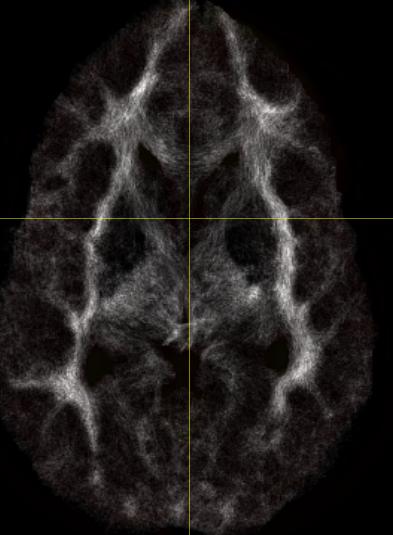

I then processed both data and created the whole brain TDI images, but

the results are quite different (see tdi_analyze.jpg and

tdi_nifti.jpg).  It appear the TDI image by using ANALYZE is what TDI

is supposed to be looked like although now it does not align with

original NIFTI data, which has made the previous co-registration

matrices useless.